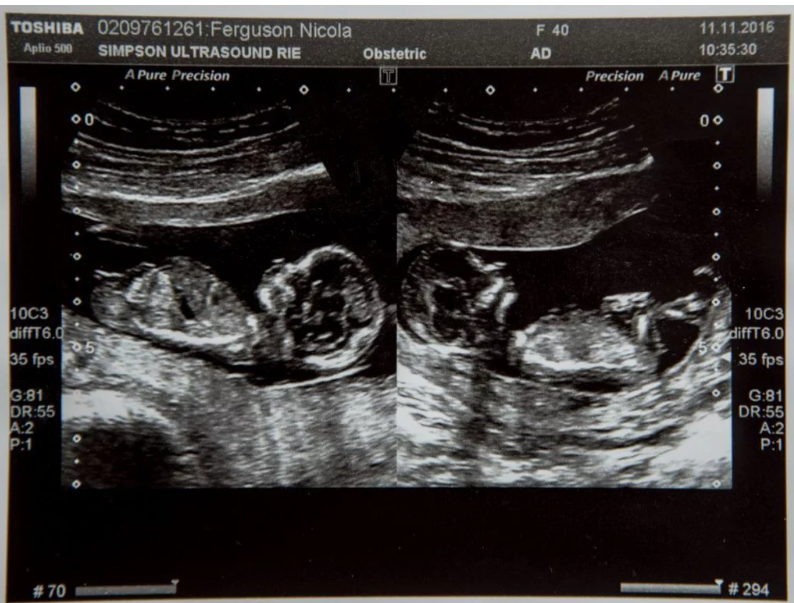

Dar la ecografia de 16 săptămâni au descoperit că gemenii lor dezvoltau probleme cardiace și medicii le-au spus că singura soluție ca cel puțin unul să supraviețuiască este cea de a-i opri forțat inima celuilalt.

La doar o zi după ce Nicky a aflat că are două fetițe, medicii i-au spus că una dintre acestea lua doar 30% din placentă. Medicii au avertizat că, dacă nu realizează o intervenție chirurgicală cu laser, ambii copii ar putea muri din cauza sindromului transfuzor-transfuzat.

Toată perioada sarcinii a fost atent monitorizată, făcea ecografii de 3-4 ori pe săptămână, iar la 30 de săptămâni, medicii au decis că este imperativ să îi facă o cezariană. Cele două fetițe au venit pe lume pe 16 martie 2017, au fost ținute în incubator mai multe săptămâni, dar în cele din urmă au supraviețuit amândouă și au fost lăsate să meargă acasă.